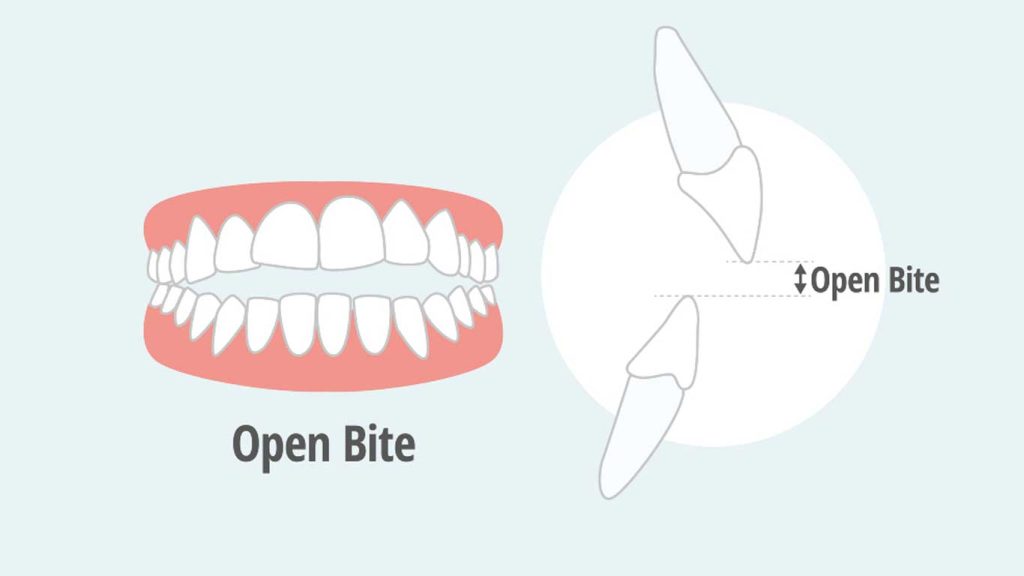

اپن بایت نوعی ناهنجاری شایع دندانی است که در آن دندان های فک بالا و پایین هنگام بسته شدن دهان به طور کامل روی یکدیگر قرار نمی گیرند. برای درمان تخصصی و مؤثر اپن بایت، می توانید به دکتر کاظم دالایی، بهترین متخصص ارتودنسی تهران مراجعه کنید که در زمینه اصلاح مشکلات بایت و ارتودنسی پیشرفته سابقه درخشانی دارد. شکل صحیح قرار گرفتن دندان ها روی هم که به آن «اُکلوژن» می گویند، نقش بسیار مهمی در سلامت فک و زیبایی لبخند دارد.

اپن بایت چیست؟

اپن بایت یکی از ناهنجاری های شایع دندانی است که در آن، هنگام بسته بودن دهان، برخی از دندان ها، معمولاً دندان های جلو یا عقب با یکدیگر تماس ندارند. این وضعیت می تواند باعث بروز مشکلاتی در جویدن، صحبت کردن، و زیبایی لبخند شود. در حالت طبیعی، دندان های بالا و پایین باید هنگام بسته شدن دهان روی یکدیگر قرار گیرند که به آن نرمال بایت گفته می شود. بایت باز ممکن است به دلایل مختلفی مانند عوامل ژنتیکی، عادت های نادرست دهانی یا اختلالات رشدی در فک ایجاد شود و معمولاً برای اصلاح آن از روش های تخصصی ارتودنسی استفاده می شود.

اپن بایت در دو نوع اصلی طبقه بندی می شود:

- اپن بایت قدامی: شایع ترین نوع اپن بایت است که در آن، هنگام بسته بودن دهان، دندان های جلویی فک بالا و پایین با یکدیگر تماس ندارند و فضای خالی میان آن ها دیده می شود. این حالت اغلب در لبخند یا هنگام صحبت کاملاً مشهود است.

- اپن بایت خلفی: در این نوع، دندان های عقبی، مانند آسیا ها در تماس نیستند، در حالی که دندان های جلویی ممکن است روی هم قرار بگیرند. این وضعیت می تواند عملکرد جویدن را به طور جدی مختل کند.

در برخی افراد، اپن بایت ممکن است ترکیبی از هر دو نوع قدامی و خلفی باشد که نیازمند بررسی دقیق تر و برنامه درمانی جامع تری است.